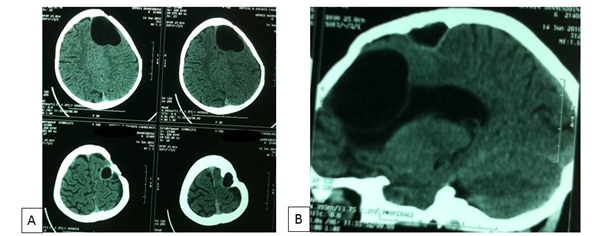

An eight-year-old girl underwent surgery for the removal of an intracerebral frontal left hydatid cyst three years ago. She didn’t take any regular medical therapy following surgery. She came with intermittent headaches and vomiting for two months. There was no history of recent trauma. Physical examination revealed a healthy child in no distress. There was no frontal syndrome. Chest X rays and abdomen ultrasonography were normal. CT scan revealed a relatively large left frontal cystic lesion of similar density to cerebro-spinal fluid, with another small separate one in the epidural space in the adjacent region close to the midline, associated to bone exostosis around the cyst without bone defect (Figure 1). No rim enhancement was seen. Laboratory tests were normal. The patient underwent a left frontal craniotomy which revealed intracerebral and epidural hydatid cysts (Figure 2). The intracerebral cyst was completely removed following the Dowling’s technique, whereas the epidural one ruptured because It was seen that the inner part of the cranium overlying the cyst was thickened and the membrane of the cyst was adherent to the cranium. The contents of the cyst aspirated without any contagion and the cavities were irrigated with warm hypertonic saline solution. The epidural cyst membrane removed totally and dura underlying was normal. The dinner table was eroded by the mass without total defect. There was no evidence to suggest that both cysts communicate between each other. The postoperative course of the patient was uneventful. CT scan control showed a complete removal of the two cysts without recurrence (Figure 3). Following the surgery, the patient received oral Albendazole (15mg/kg/day). She is doing well at 6months follow-up.

Figure 3 Post-operative CT scan showing the complete removal of the cysts without recurrence.